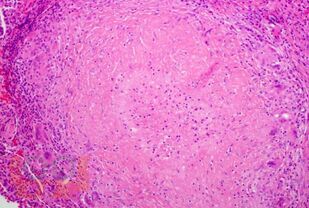

Изложены современные данные о туберкулезе орофациальной локализации. Раскрыты вопросы этиологии, классификации, патогенеза, факторов риска, особенностей клинической картины, диагностики, дифференциальной диагностики. Представлены алгоритм обследования пациентов с подозрением на орофациальный туберкулез и особенности лечения заболевания В виду редкой локализации заболевания учебный материал проиллюстрирован клиническими данными больных с верифицированным орофациальным туберкулезом, которые общедоступны и опубликованы в сети интернет в профильных журналах. Тесты представлены в различных модификациях, ответы на ситуационные задачи ориентируют на практику, что завершает качественное и полное освоение учебной дисциплины. Пособие разработано к рабочей программе модуля «Инфекционные болезни, фтизиатрия» по блоку фтизиатрия для направления подготовки 31.05.03 – Стоматология для студентов высших медицинских образовательных учреждений и рекомендуется к использованию для самостоятельной подготовки к занятиям и углубленного изучения материала.